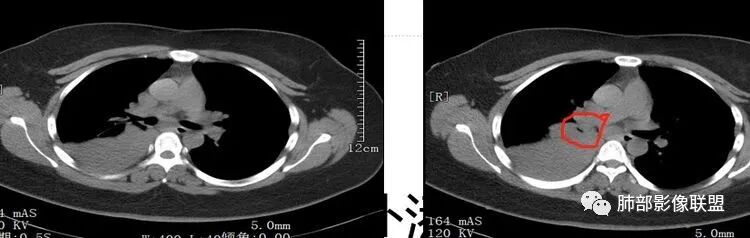

我们捋一捋病灶的范围

这是上叶血管

我再捋一捋支气管

右主支气管

上叶支气管

中间段

争议的地方这是上叶?中叶?

说实话图不全

关键点——中间段支气管堵塞处

没有显示

都是以肺内的病变为主

其实关键点在中间段支气管

通过视频显示中间段堵了

支气管腔内占位

远端低强化,提示粘液很多

纵隔淋巴结大

本病例特点是中叶病灶和下叶病灶不一样,支气管腔内的病灶又是怎么样的呢?我们要是有沿支气管重建的冠状位、矢状位会更有利于分析。第一,中叶病灶明显粘液样改变、低密度,且低密度区有占位效应、膨隆,确实要考虑粘液表皮样癌。第二,中叶和下叶支气管显示不出来,但血管显示出来了。中叶病灶血管稀疏、细小,下叶病灶血管粗大、走形正常。朝外肺不张实变,不是单纯的肺不张,肺不张一般体积明显缩小、血管聚拢,该病例肿瘤于其中成分不一样,所以上叶部分病灶考虑为下叶病灶占位效应及膈面向上推压引起,中叶萎缩。综合腔内堵塞、纵隔淋巴结肿大要考虑恶性。

支气管层面位置朝下强化明显,支气管腔内、远端是有差异的,腔内哪些是粘液?哪些是肺组织?是单纯实变?还是合并感染?还是外围都是病变?支气管腔内病变?

该病灶明显实变,需鉴别是内朝外,还是外朝内病变。该病灶内血管走形自然,肺门区血管无明显受压移位,且非起源于胸膜,不张肺组织或者不张肺组织夹杂炎性病变。而非典型肺炎型肺癌及外朝内的其他恶性病变。

内朝外病变是支气管腔内病变?还是支气管周围病变呢?如果支气管周围大恶性肿块灶,那其内血管也不应走形自然,应杂乱无章,所以只能是腔内病变引发支气管周围病变。